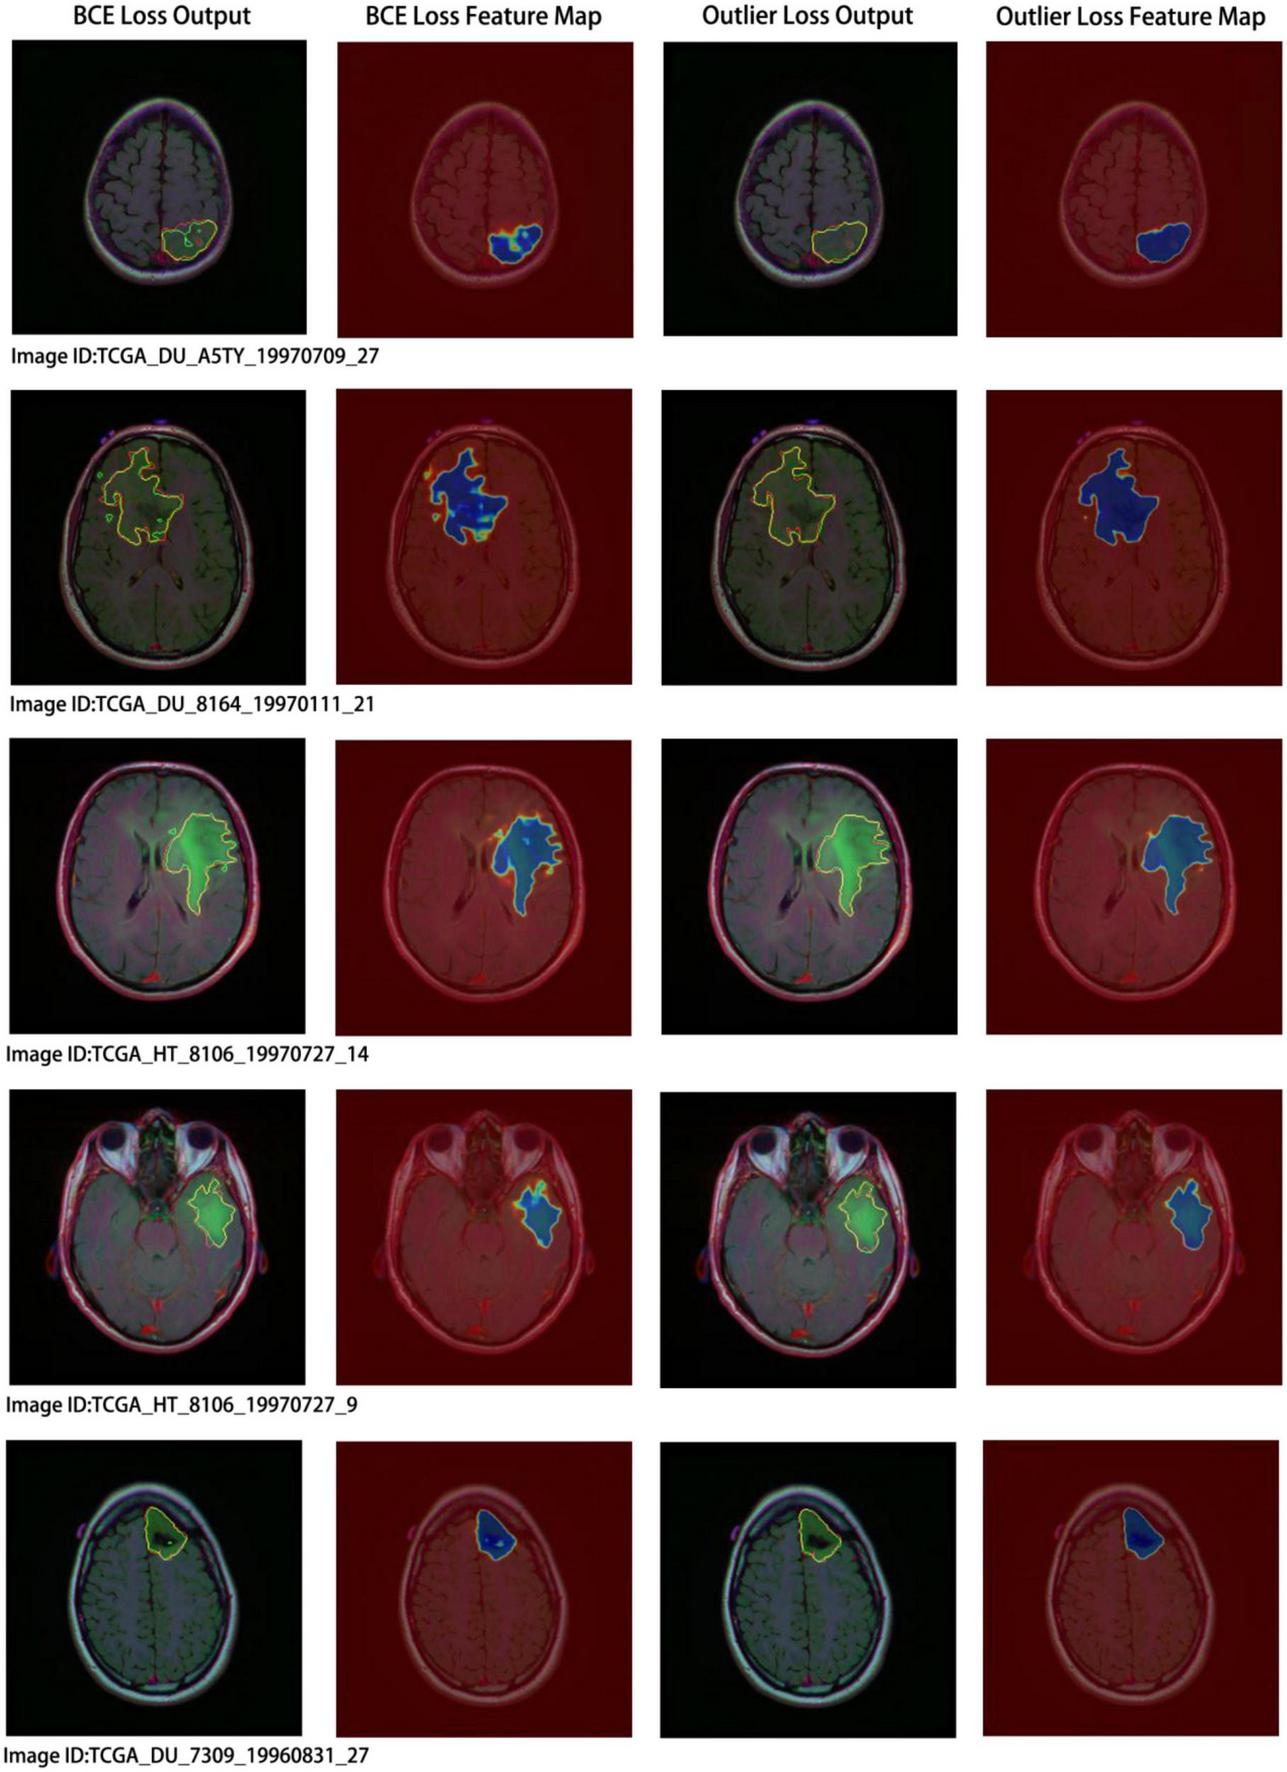

Concurrently, we performed a visual analysis on a subset of images, as shown in Figure 7. The first and second columns indicate the segmentation results and probability heatmaps obtained using BCE loss, whereas the third and fourth columns show the segmentation results and probability heatmaps obtained using outlier loss. The red and green lines in the segmentation results represent the ground truth and predicted labels, respectively. The probability heatmaps represent the confidence of the predictions: darker colors indicate higher confidence. From the comparison of the predicted segmentation results, it is evident that the use of outlier loss significantly reduces the occurrence of noise and improves the edge fitting effect, thereby greatly enhancing the quality of the segmentation results. Furthermore, in the comparison of the predicted probability results, the use of outlier loss leads to fewer intermediate colors in the edge regions, indicating higher confidence and better model performance. The foreground region exhibits a higher consistency in color, indicating a smaller variance in the overall predicted results for the foreground region and a more stable segmentation effect. In contrast, the use of BCE loss results in lower color consistency for the foreground region, indicating a larger variance in the overall predicted results for the foreground region and poor segmentation performance.

FIGURE 7

Segmentation results and visual analysis obtained using different loss functions. The first and second columns show the segmentation results and probability heatmaps obtained using the binary cross-entropy (BCE) loss, while the third and fourth columns show the segmentation results and probability heatmaps obtained using the outlier loss. In the segmentation results, the red line represents the ground truth label, and the green line represents the predicted result. The probability heatmap represents the confidence of the prediction: darker colors indicate higher confidence.